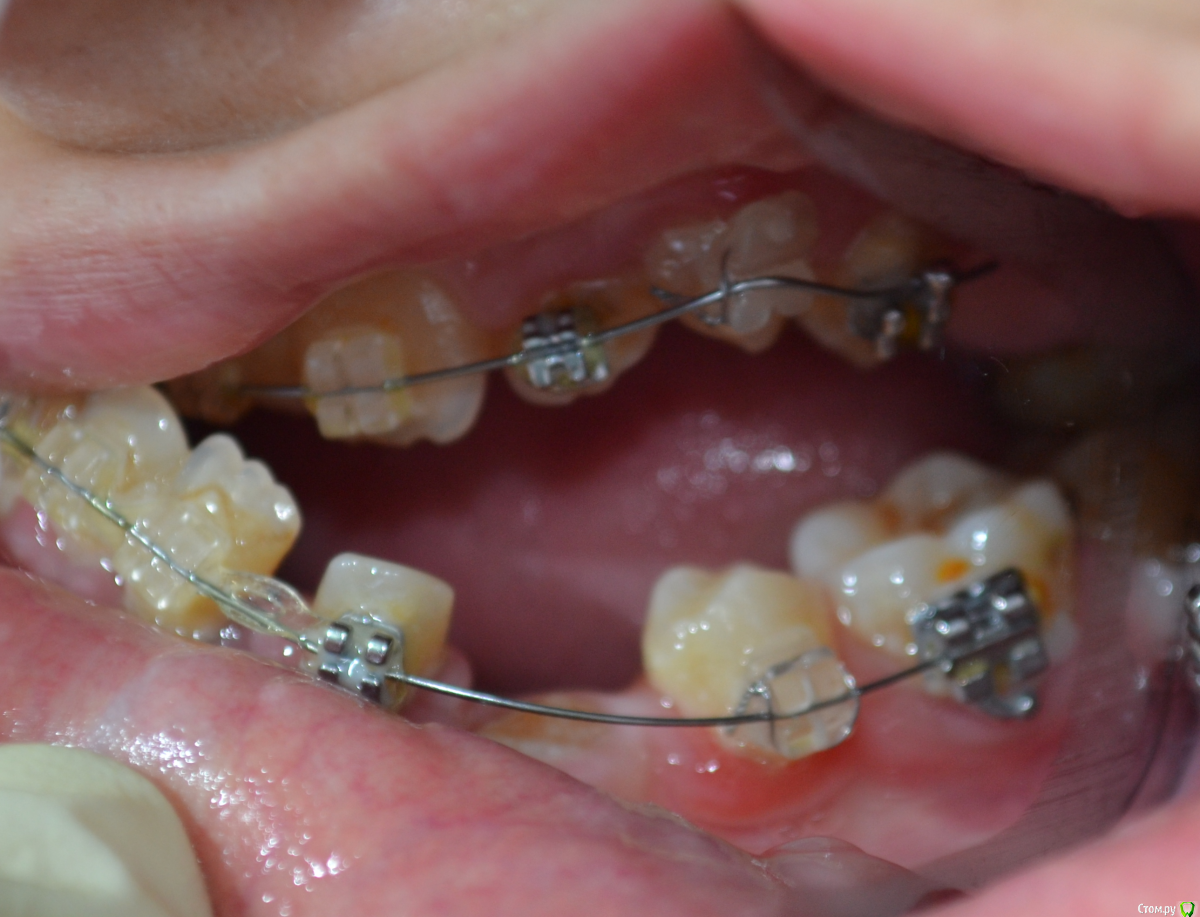

nikor117 Опубликовано 14 октября, 2015 Поделиться Опубликовано 14 октября, 2015 Здравствуйте, уважаемые коллеги.Извиняюсь за качество фото. Хотелось бы помочь пациентке 28 лет. В общем ситуация видна по фото. Сам я ортопед опыта в таких ситуациях нет, возможно подскажете куда ей стоит обратиться. Заранее спасибо. Если нужна дополнительная информация скажите постараюсь выложить. Ссылка на комментарий

nikor117 Опубликовано 14 октября, 2015 Автор Поделиться Опубликовано 14 октября, 2015 Возможность красиво улыбаться, с ее слов на ортодонтии она уже порядка 8 лет, брекеты стоят 1.5 или 2 года, сама врач, сложность ситуации представляет, хочет услышать совет Ссылка на комментарий

Yana guapa Опубликовано 14 октября, 2015 Поделиться Опубликовано 14 октября, 2015 эти фото были ведь на соседнем форуме "...." . там были советы, и хирурги и ортодонты отписывались. причем не так давно. и фото были без брекетов, до начала лечения (около 6 месяцев назад). не похоже на 1.5 года с брекетами здесь . тем, что у нее на зубах стоит сейчас - не помочь это точно. 4 Ссылка на комментарий

Monkey Опубликовано 18 октября, 2015 Поделиться Опубликовано 18 октября, 2015 (изменено) и мне, пожалуйста у пациентки похоже синдром Крузона Изменено 18 октября, 2015 пользователем Monkey 1 Ссылка на комментарий